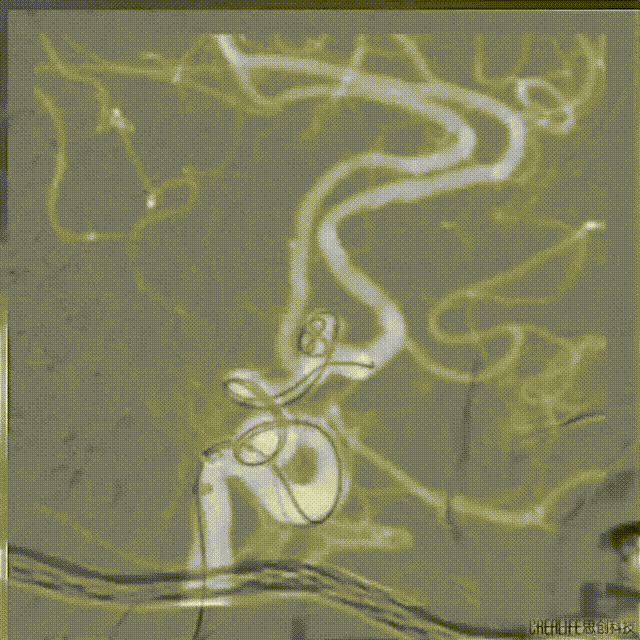

手术精华

同轴技术建立通路:8F导引导管到位右颈内动脉C1段,6F 沃比中间导管送达海绵窦段。路图及微导丝指引下将塑形微导管送达前交通动脉瘤体处上部。

填塞Target 3*8mm弹簧圈半释放,另选SL-10微导管,微导丝指引下超选至同侧大脑前动脉A2段以远。

送入Atlas 4*21mm支架,释放并充分覆盖瘤颈,继续填塞弹簧圈成篮。

依次填塞Target 2mm*6cm、2mm*4cm弹簧圈、Prime 2mm*4cm、2mm*4cm、2mm*4cm弹簧圈、Target 2mm*3cm弹簧圈、Prime 1.5mm*4cm、1.5mm*3cm弹簧圈。

工作角度,见瘤体填塞致密。

正侧位造影。